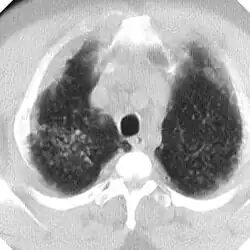

La silicosis complicada se caracteriza por la presencia en los pulmones de masas de diámetro superior a 1 centímetro llamadas masas de Fibrosis Masiva Progresiva (FMP) que al retraerse generan bullas en su periferia y distorsionan los bronquios determinando obstrucción y limitación del flujo aéreo, aparte de otras complicaciones (neumotórax, cavitación aséptica, cavitación por tuberculosis, etc). Si las masas alcanzan cierto tamaño alteran notablemente los parámetros de función pulmonar, tanto de ventilación como de intercambio de gases. Silicosis aguda, la cual resulta de la exposición a cantidades muy grandes de sílice durante corto tiempo. Los pulmones se inflaman bastante y se pueden llenar de líquido, lo que causa una dificultad respiratoria grave y una baja de los niveles de oxígeno en la sangre.

En caso de dudas diagnósticas se puede recurrir a la Tomografía Computada de Alta Resolución (TACAR) que se ha mostrado más sensible y específica para el diagnóstico.[9] Somete al paciente a mucha más radiación que la Rx y no debe usarse como prueba diagnóstica de primer nivel sino para aclarar dudas. La TACAR permite comprobar cómo las masas de FMP se originan frecuentemente en región subpleural de zonas apicales posteriores desplazándose progresivamente de la pleura —signo del desprendimiento—.[3]